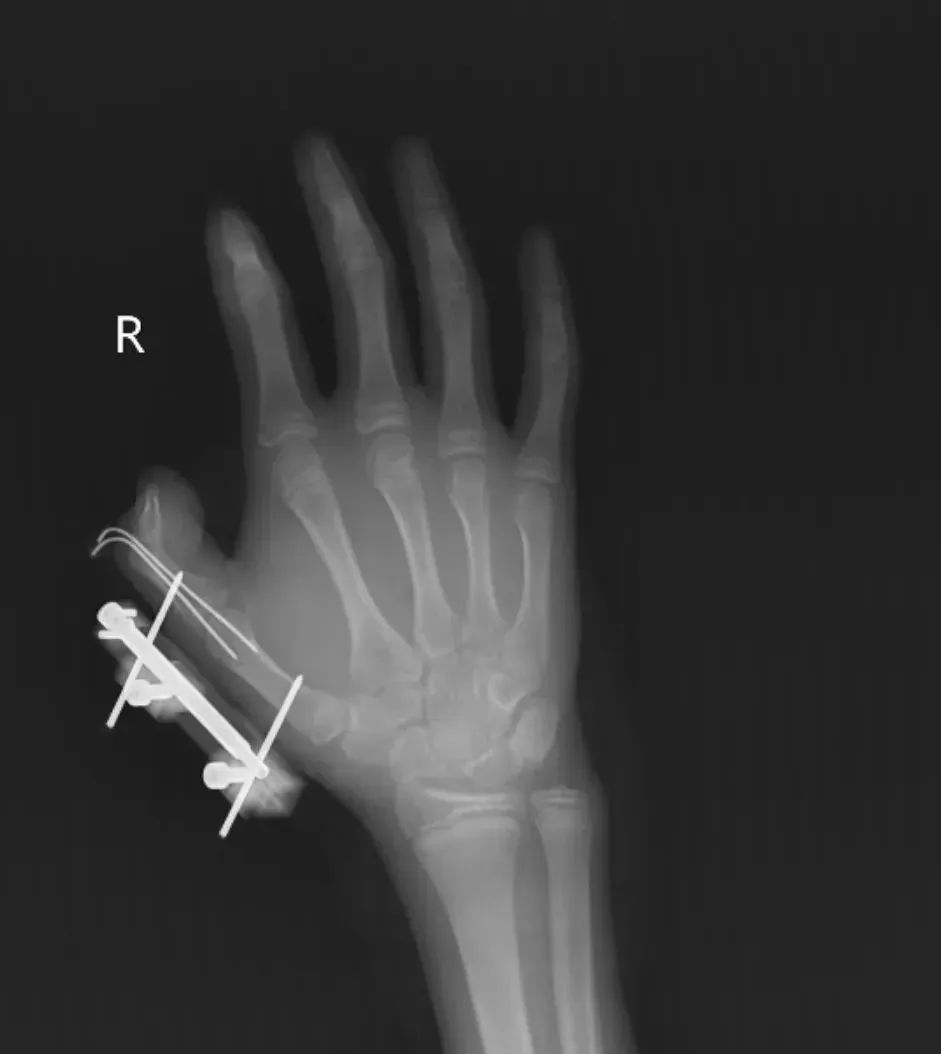

Mới đây, tại tỉnh Hồ Nam, Trung Quốc, một bé gái 14 tuổi (tên gọi là Vi Vi) phát hiện túi đá khô trong hộp kem vừa đặt mua online. Nghĩ rằng đó chỉ là loại đá bình thường, em đem túi đá khô lắc chơi trong tay. Chỉ vài giây sau, túi kín đựng đá khô bất ngờ phát nổ. Vụ nổ khiến tay phải của Vi Vi rách một đường khoảng 10cm ngay vị trí kẽ ngón cái, cơ bị đứt, lộ mô mềm, kèm theo gãy xương và trật khớp. Ngón cái hoàn toàn mất cảm giác.

Vi Vi đã được phẫu thuật giữ lại ngón tay, nhưng bác sĩ cho biết phải phục hồi chức năng dài hạn mới hy vọng lấy lại khả năng cầm nắm tinh tế.